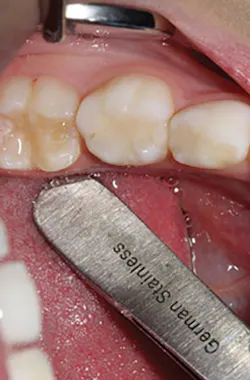

The steps for preparation and cementation were as follows. First, local anesthesia was delivered. Second, isolation was achieved with an isolation system (Isodry). Third, preparation steps were undertaken: Occlusal preparation was completed using a high-speed handpiece with copious amounts of water and a coarse, long-tapered diamond bur (NuSmile) to achieve an occlusal reduction of 1.5–2 mm. Circumferential reduction of approximately 15–20% was carried out using the same bur. In order to visualize the completeness and evenness of the preparation, a full circumferential reduction supragingivally was completed at this stage. A subgingival preparation was again completed using a high-speed handpiece with copious water and a finer, more tapered diamond bur (NuSmile). As required, a full subgingival reduction to approximately 1.5 mm depth was achieved, ensuring no ledges and a smooth featheredge margin (figure 2). It was essential that the crown fit passively and be able to be seated completely unencumbered. In order to ensure fit and occlusion and to prevent contamination of the zirconia crown to be cemented, a Try-In crown (NuSmile) was used (figure 3). Refinements to the preparation to facilitate fit and occlusion were done at this point.

Figure 3: Try-In crown (NuSmile)